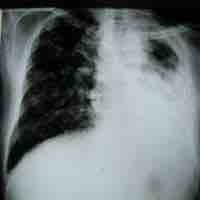

Antimycobacterial antibiotics target microbes classified as mycobacterium.

Antimicrobial resistance is a major public health and economic burden on patients, affected communities, and healthcare providers.

Antimicrobial resistance has created a public health crisis in the treatment of infectious diseases and necessitates the discovery of new drugs.